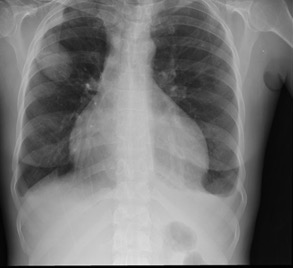

CXR/HRCT shows bilateral interstitial pulmonary opacifications

Image 1: Yale Rosen from USA / CC BY-SA (https://creativecommons.org/licenses/by-sa/2.0)